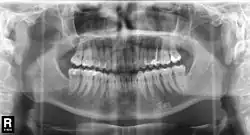

En 1934, le Japonais Hisatugu Numata met au point le premier appareil à panoramiques X dentaires. La mise au point de l'appareil intraoral, où le tube émetteur se trouve à l'intérieur de la bouche et le film à l'extérieur suit. En parallèle, Horst Beger, de Dresde, en 1943 et Walter Ott, dentiste suisse, en 1946 mettent au point les appareils Panoramix (Koch & Sterzel), Status X (Siemens) und Oralix (Philips)[129]. Le Finlandais Yrjö Veli Paatero (1901–1963) continue à mettre au point la technique et donne à l'appareil le nom de Parabolographie, puis de Pantomographie en 1950, et enfin sur la suggestion du Japonais Eiko Sairenji le nom Orthopantomographie en 1958[130],[131],[132]. Le premier de ces appareils est distribué en 1961 sous le nom de Panorex par la firme S.S. White[133]. Les tubes émetteurs et le film y tournent de façon synchrone autour de la tête du patient. À la fin des années 1980, les appareils panoramiques intraoraux sont abandonnés définitivement, parce que la dose de rayonnement par le tube en contact avec la langue et la muqueuse buccale se trouve trop élevée.

En 1987, Trophy Radiology (France) a mis sur le marché le premier appareil à rayons X numérique pour images dentaires intra-orales sous le nom de Radiovisiographie. En 1995, DXIS, le premier appareil panoramique dentaire numérique est introduit par Signet (France), suivi en 1997 par SIDEXIS, (Siemens, plus tard Sirona) avec Ortophos Plus. Au lieu d'un film, les appareils contiennent un scintillateur, qui transforme les photons X incidents soit en lumière visible soit directement en impulsions électriques. Les données captées dans le détecteur sont renvoyées sous forme numérique à l'écran d'un ordinateur[134].